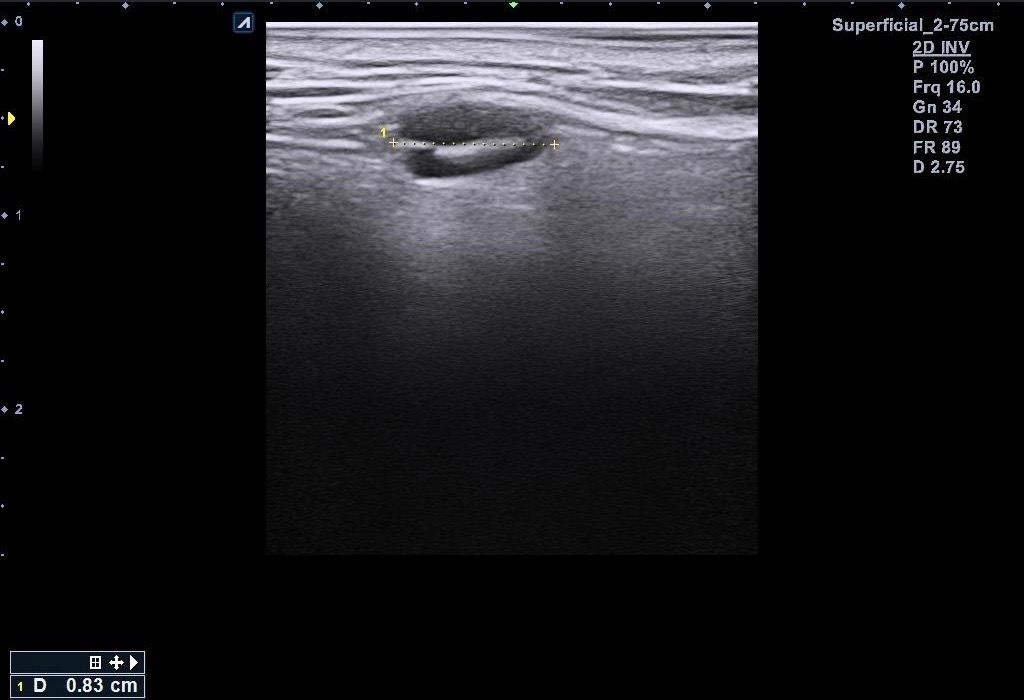

근데 병원에서 지방종이 아니라 임파선 같다고 일단 초음파 본다고 하시고 초음파를 봤는데 의사선생님이 귀 옆에 있는 임파선은 괜찮은데 아래에 있는 임파선이 초음파로 볼때 모양이랑 뭐가 조금 이상하다고 하시면서 대학병원 가보라고 소견서를 써주셨습니다 (소견서랑 초음파사진 첨부할게요)

설명들을때 기억상으로는 1 2번째 초음파사진이 귀 아래였던 거 같아요

• 2번 째 사진

소견서에 따르면, 귀주위 임파선 비대가 있는 환자로서 초음파상 1cm 미만이지만 무증상에 hypervascular하고 귀 밑은 stalk이 잘 안 보인다고 언급되어 있습니다. 크기가 크지 않고 경계가 불규칙하지는 않아 악성의 가능성은 높지 않다고 판단 됩니다. 안내받으신대로 추가검사 및 추적관찰 하시기 바랍니다.